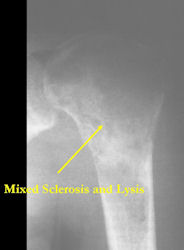

There are 3 radiographic presentations for osteosarcomas, depending upon the amount of osteoid/ossification and calcium deposition:

- Mixed sclerotic and lytic, permeative lesion most common radiographic presentation

Conventional osteosarcomas are permeative lesions on plain radiographs (borders of the lesion cannot be clearly delineated)

- Wide zone of transition from lytic/sclerotic areas of tumor to normal bone

- Makes borders of lesion hard to define